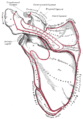

الحواف

الحافة الجانبية الوحشية سميكة وغير منتظمة، وهناك ثلاث أو أربع حديبات للمنشأ الوتري للعضلة المثلثة (الدالية). حافتها الوسطي الإنسية أقصر من الوحشية وهي مقعرة ، ويتصل عليها جزء من العضلة شبه المنحرفة، وفي وسطهاتقريبا سطح بيضاوي صغير للتمفصل مع النهاية الأخرمية للترقوة.[1]